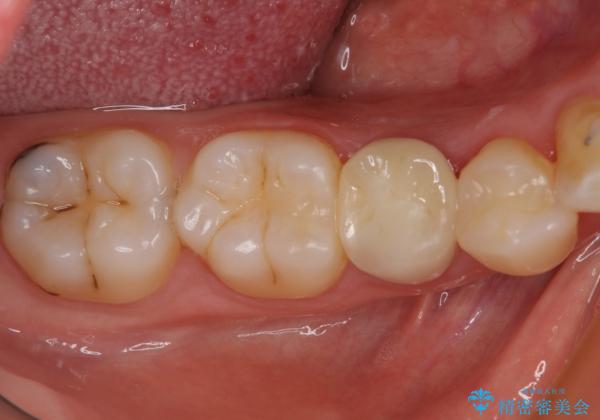

丈夫なクラウンを装着できただけでなく、形態や色調も自然に仕上げることができました。